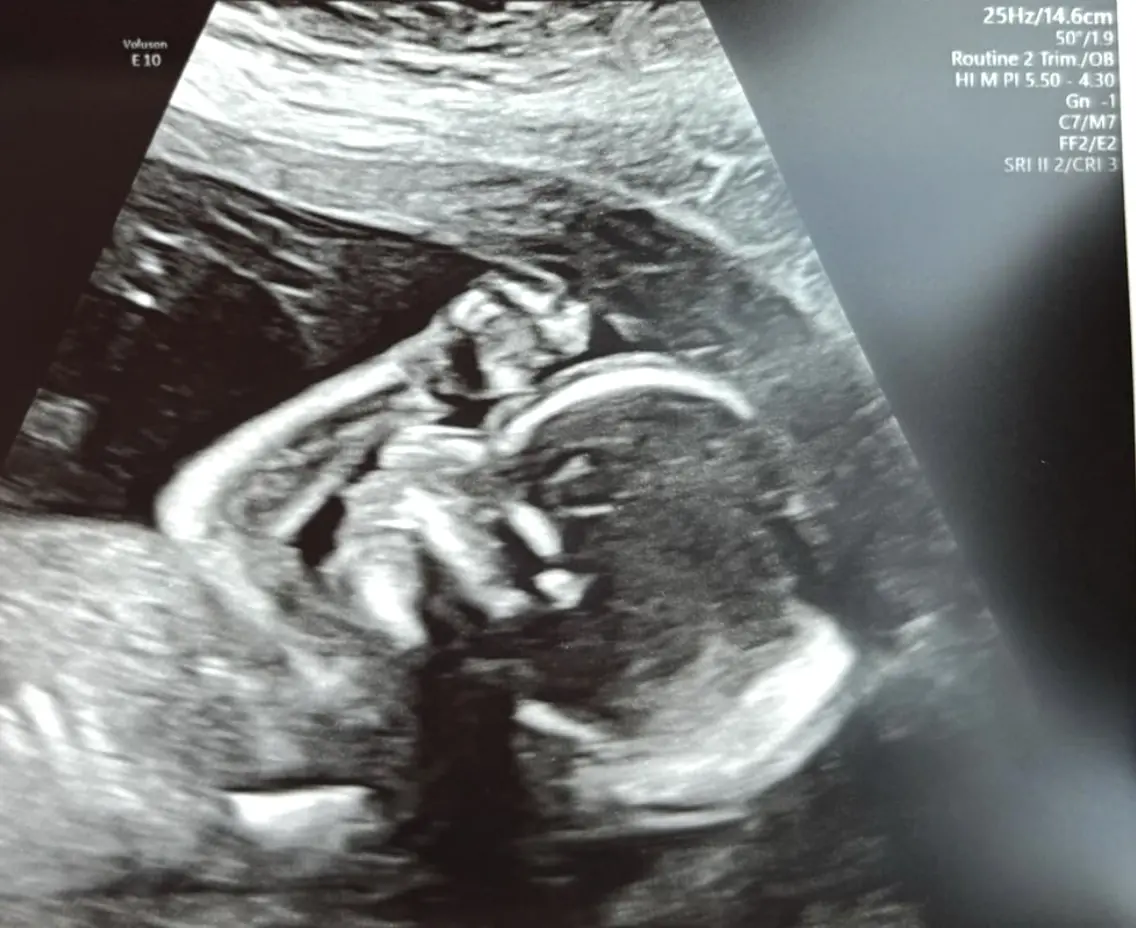

On Tuesday, Blanchard shared a sonogram image from her 20-week checkup on social media.

However, there was one detail that left some fans concerned.

Some were quick to point out that she had not blurred out the name of her OBGYN (a doctor of obstetrics and gynecology), raising concerns about her privacy.